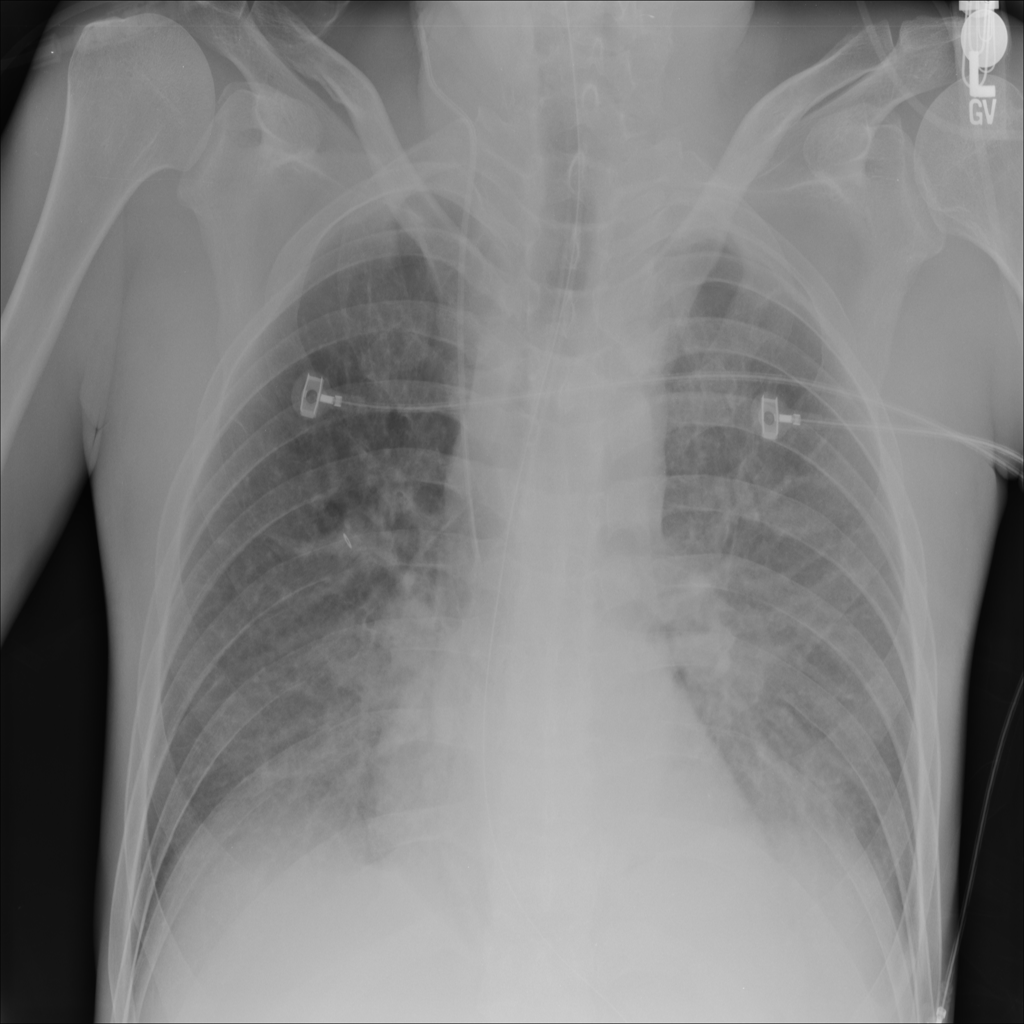

PAT-24D9 · IMG-006Edema

PAT-24D9 · IMG-006

AP